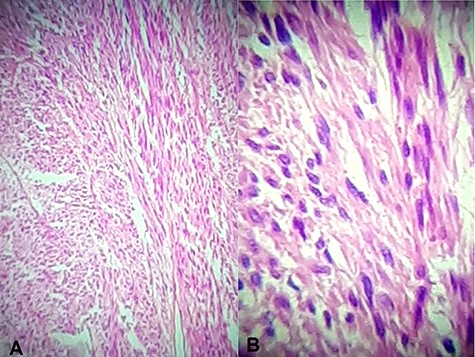

Immunohistochemical staining for CD 117 was positive confirming the diagnosis of a GIST (Fig. 6). Molecular assessment for c-KIT D816V and PDGFRA D842V mutations (markers of resistance to adjuvant imatinib therapy) were performed and were negative. Thus adjuvant imatinib 400 mg/day was commenced.

Immunohistochemical staining for CD117 (A) Jejunal mass at ×4 magnification, (B) jejunal mass at ×40 magnification is diffusely positive.